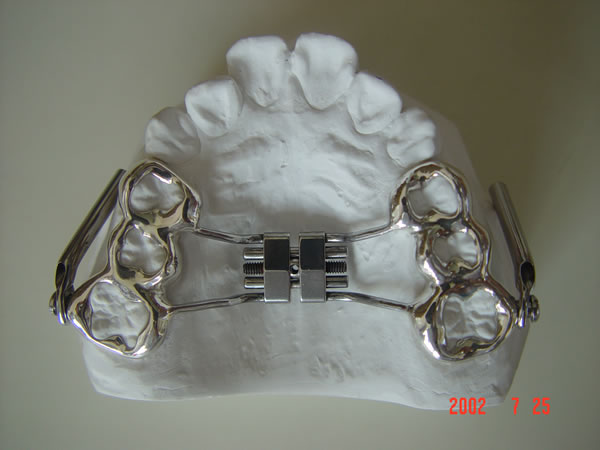

二、正畸治疗

2、固定矫治器 它粘固在牙齿上,可以精确地移动牙齿,能够矫治各种复杂的错合畸形,矫治效果好,是目前国内外最常使用的矫治器。各种固定矫治器大都由带环、矫治弓丝、托槽等三部分组成。我国自从开展固定正畸以来,先后用过Begg细丝弓矫治器、方丝弓矫治器、直丝弓矫治器来矫治错合畸形。目前国内普遍采用的是直丝弓矫治器。按照直丝弓托槽的槽沟角度的不同设计,常用的直丝弓矫治器又可分为Roth系列直丝弓矫治器、OPA-K直丝弓矫治器、MBT直丝弓矫治器等。按照托槽所用材质的不同,可以分为国产金属托槽、进口金属托槽、生物陶瓷托槽。